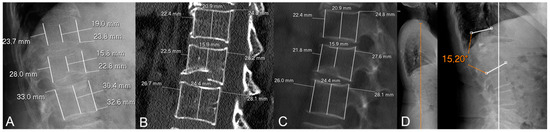

| Loss of anterior height (X-rays) | 26.1 ± 15.8 | 29.3 ± 17.8 | 22.9 ± 12.9 | 0.054 |

| Loss of middle height (X-rays) | 29.9 ± 12.3 | 32.4 ± 13.2 | 27.4 ± 11.0 | 0.052 |

| Loss of posterior height (X-rays) | 9.5 ± 10.3 | 12.3 ± 11.1 | 6.7 ± 8.7 | 0.009 * |

| Loss of anterior height (CT) | 19.5 ± 14.1 | 23.5 ± 14.9 | 15.6 ± 12.1 | 0.007 * |

| Loss of middle height (CT) | 25.5 ± 14.1 | 28.1 ± 15.5 | 22.8 ± 12.2 | 0.074 |

| Loss of posterior height (CT) | 7.8 ± 8.5 | 9.7 ± 10.0 | 5.9 ± 6.1 | 0.032 * |